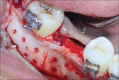

The interdisciplinary collaboration of periodontics and orthodontics has allowed teeth to be moved 2-3 times faster, reducing the time required for traditional orthodontic therapy considerably. Periodontally accelerated osteogenic orthodontics (PAOO), also known as Wilckodontics, is a combination of a selective decortication facilitated orthodontics and alveolar augmentation. With this technique, there is no dependence on the pre-existing alveolar volume. This case report describes the treatment of permanent mandibular molar protraction in a 14-year-old patient undergoing orthodontic therapy using PAOO with piezosurgery.